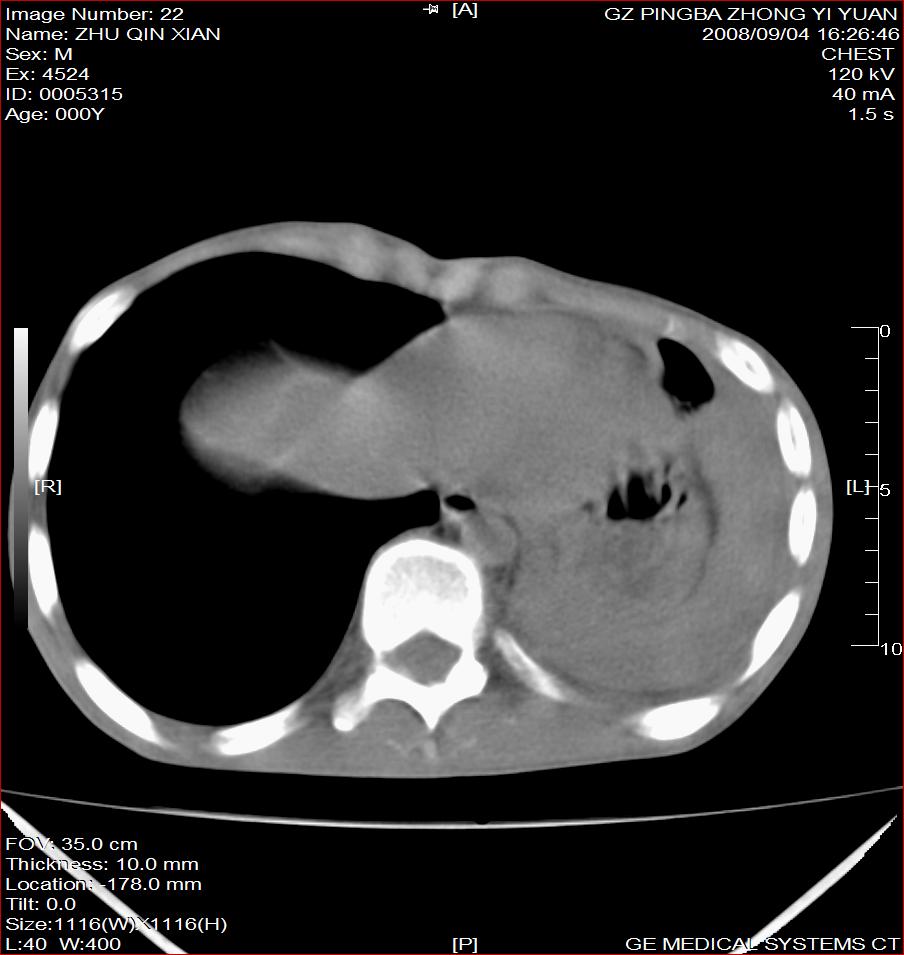

以下是引用随光逐影在2008-9-4 20:05:00的发言:[br]1)考虑两肺结核。2)左侧胸膜炎(胸膜肥厚、粘连,胸腔积液)。3)左侧局限性气胸。

以下是引用子十在2008-9-4 19:34:00的发言:[br]左上肺结核并空洞及双肺播散。节段性肺不张、胸腔积液、胸膜肥厚粘连。[br]